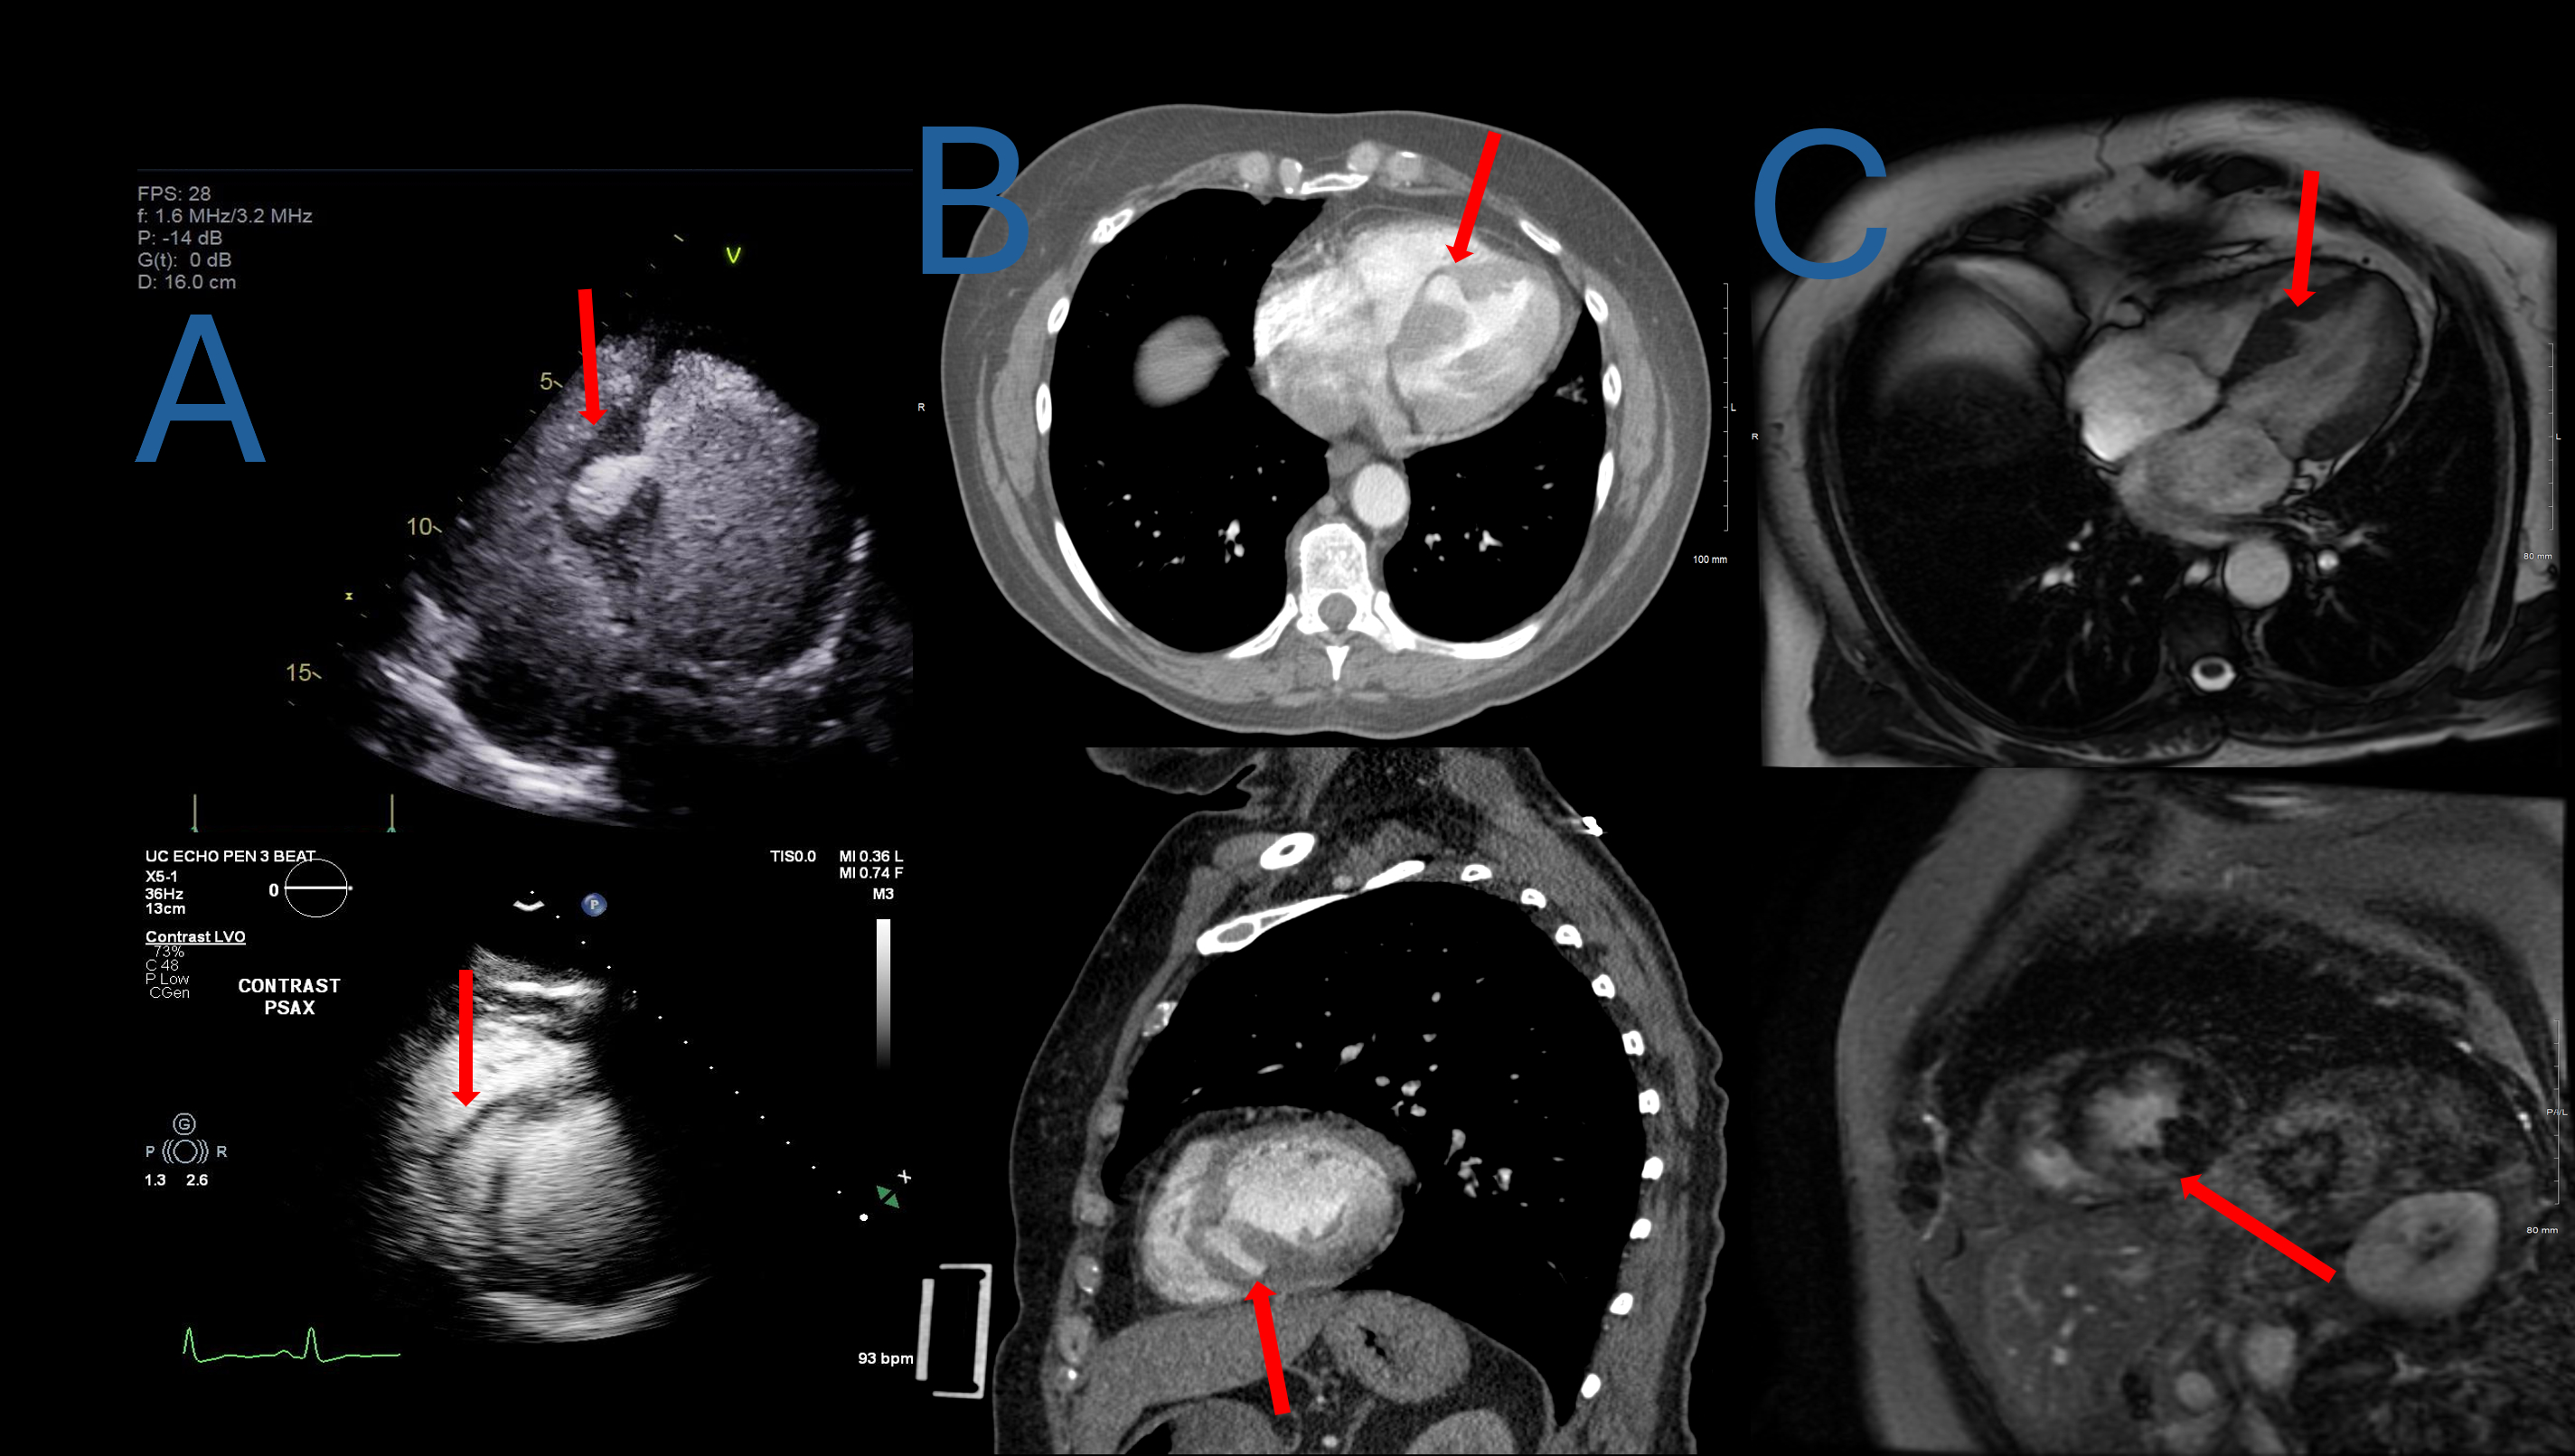

A healthy 55-year-old female presented after blunt chest trauma from a car accident. Bedside echocardiogram revealed a mid-septal LV discontinuity with myocardial outpouching. Lab work was significant for high sensitivity troponin of 22,000 ng/L which peaked at 24,000 in 5 hours. ECG revealed normal sinus rhythm with a QRS duration of 102ms. No ventricular ectopy was detected. Transthoracic echocardiograph (TTE) using echo contrast agent and computed tomography (CT) scan confirmed the intraventricular pseudoaneurysm (Fig 1-A&B).

A transesophageal echocardiogram (TEE) showed an intact PSA at 3.7 x 2.5 cm LV PSA with a 5mm neck extending from the mid septum superiorly into the right ventricle (RV) with no Doppler evidence of rupture or shunt (Fig 2). With cardiology and cardiac surgery shared decision making, conservative therapy was elected in the setting of polytrauma and hemodynamic stability. Serial TTEs showed stable size and appearance of the PSA during her month long hospitalization.

Cardiac magnetic resonance imaging (cMRI) 7 months later showed significant improvement in the PSA size to 0.3 cm2 and extensive myocardial remodeling (Fig 1-C).

LV septal PSA is rare following blunt chest trauma, and it confers a considerable risk of rupture with the highest risk occurring within 3 months of formation. Untreated PSA presents with risks including thromboembolism, infection, and arrhythmia. Multimodal cardiac imaging is paramount for diagnosis and surveillance. There are no guidelines for serial monitoring in hemodynamically stable patients and an individualized approach should be taken. In this patient TTE, TEE, and CT imaging modalities were utilized. Our patient progressed without complication following conservative management with shrinking and scarring of the aneurysm characterized by the cMRI.